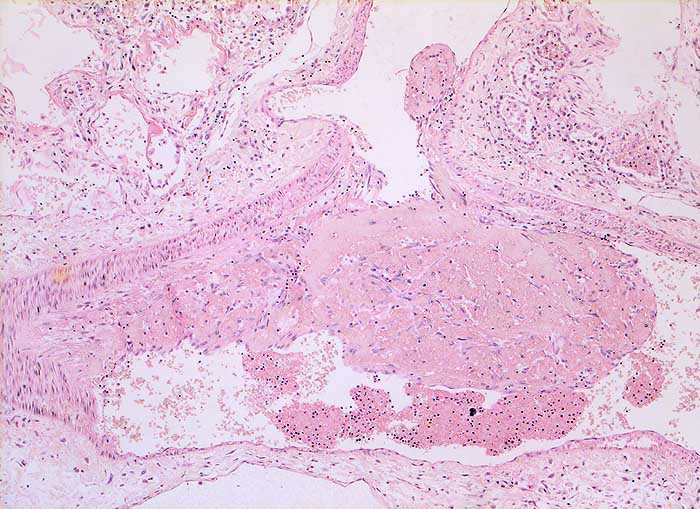

PathoPic – image database / PathoPic ID 5551 - Diffuser Alveolarschaden: proliferative Phase

Diffuser Alveolarschaden: proliferative Phase

Grössere Arterie mit partiell organisiertem wandadhärentem Thrombus. Im angrenzenden Parenchym sind hyaline Membranen erkennbar.

Gefässveränderungen in Form von Thrombosen und fibroproliferativen Veränderungen gehören mit zum Krankheitsbild des diffusen Alveolarschadens. In der akuten Phase überwiegen frische Thromben. In der proliferativen Phase (vorliegender Fall) findet man vor allem Thromben in Organisation.